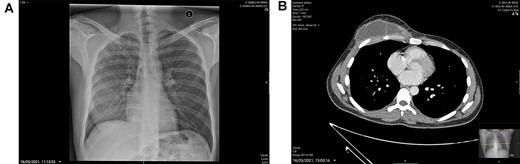

A 31-year-old healthy south-east Asian male presented as a general surgical emergency to a tertiary care facility with a 3-month history of a mass on the right side of his chest. It had progressively increased in size and become painful and erythematous days prior to his presentation. He reported no fevers, shortness of breath, cough, night sweats or weight loss. On examination, it was thought to be a suppurative chest wall abscess (Fig. 1). His inflammatory markers on admission bloods were within normal range. His chest X-ray showed, ‘linear and nodular densities in the right upper zone suggestive of an acute inflammatory process and a new ill-defined density overlying the right lower zone’ (Fig. 2A). Due to concerns of the abscess fungating into the breast or chest wall, he had a computerized tomography (CT) scan of his thorax with contrast. This showed a ‘10 × 4.5-cm mass with internal septations and surrounding fat stranding, arising from the anterior chest wall, with no bony destruction of the fifth anterior rib (Fig. 2B). There were signs of old TB within the lungs with tree-in-bud changes within the right apex suggestive of an acute on chronic infection’.

(A) Chest X-ray: linear nodular density right upper lobe. (B) CT Thorax at presentation showing the right-sided anterior chest wall, septating mass highly suspicious of a TB infection.